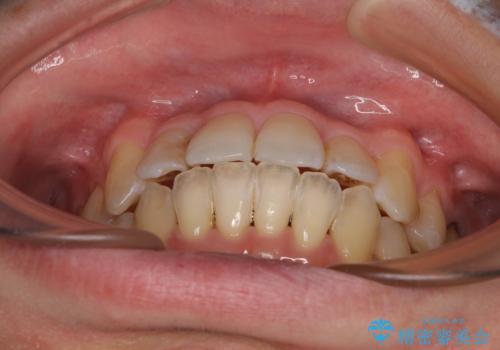

前歯のクロスバイト 目立たないワイヤー装置で矯正治療

- 前歯のクロスバイトを改善したいとのことで来院された患者様です。

マウスピース矯正では前歯の神経への負担が大きいことを懸念され、ワイヤー装置による矯正治療を行うこととしました。

舌の突出癖が認められたため、デコボコ改善に伴い前歯が前突する可能性があったため、舌のトレーニングをしっかりと行うよう指導しながら治療を進めることとしました。